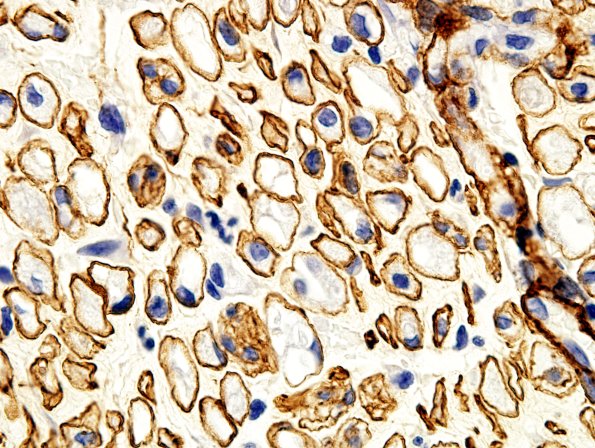

Washington University Experience | PERIPHERAL NEUROPATHY | 4 AXONAL DEGENERATION | 1 H&E & IHC | 1C2 Regeneration Coll IV (Case 1) bA

These degenerating/regenerating axons demonstrate Schwann cell nuclei and, in some cases, macrophages within the original basement membrane of the axon. (Collagen IV) IHC)